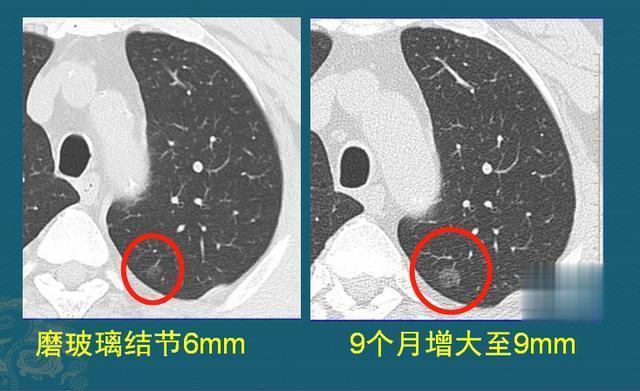

一般情况下,肺结节越大恶性概率越高,但是并非百分百,比如一些炎症结节就可能在极短时间内快速长大超过10mm;

另外,除了大小以外,还要看结节是否有相关的恶性特征。

比如毛刺征、分叶征、空泡征、胸膜牵拉症、血管集束征等,含有的特征越多则恶性风险越高。